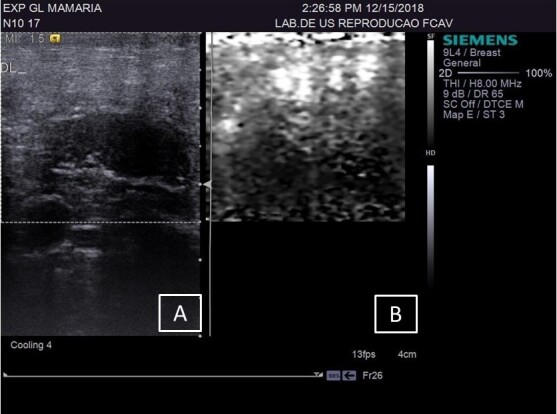

该研究旨在评估在乳腺实质和乳腺上淋巴结中使用Acustic Radiation Force Impulse(ARFI)弹性成像技术检测自然感染慢性纤维性病变绵羊活动性乳腺炎的情况。研究人员选取了 27 只雌性绵羊,采集了 48 个乳腺的 B 型超声波和 ARFI 弹性成像图像,获得了定性(回声和回声纹理)和定量(剪切率、深度和长短轴比)变量。这些乳腺被分为三个实验组:对照组(CG)--健康动物;LSCC--出现纤维性病变和 SCC(体细胞数)小于 500 x 103 cls/mL的动物;HSCC:出现纤维性病变和 SCC(体细胞数)大于 500 x 103 cls/mL的动物。在腺体的健康区域,LSCC 的剪切波速度(SWV)比 HSCC 高(P=0.04)。将 LSCC 组和 HSCC 组的纤维化部位与各自的正常部位进行比较时,两组的剪切波速度都有所增加:LSCC(p= 0.0007)和 HSCC(p= 0.0001)。将 LSCC 和 HSCC 的纤维化区域与 CG 实质进行比较,LSCC(p=0.001)和 HSCC(p=0.0001)的纤维化区域均有所增加。B 型超声显示,在活动性亚临床乳腺炎病例中,淋巴结以低回声为主,短/长轴比值降低。CG 组与 HSCC 组(P=0.02)和 GC 组与 LSCC 组(P=0.04)相比,乳腺上淋巴结的 SWV 增加。B 型超声波检查有助于评估乳腺实质,但不建议将其作为独立的诊断技术使用。ARFI 弹性成像显示了区分亚临床乳腺炎和痊愈乳腺炎的潜在临界点,突出了其作为区分正常区域和纤维实质区域工具的重要性。虽然由于样本量的限制,本研究没有确定具体的临界点,但更大样本量的进一步研究可以探索和确定这些关键临界点。

The aim of the study was to evaluate the use of Acustic Radiation Force Impulse (ARFI) elastography in mammary parenchyma and supramammary lymph nodes, for detection of active mastitis in sheep with naturally infected chronic fibrous lesions. 27 female sheep were included and B-mode ultrasound and ARFI elastography images were obtained, acquiring qualitative (echogenicity and echotexture) and quantitative (shear rate, depth and short/long axis ratio) variables of 48 mammary glands. The glands were divided into three experimental groups: control group (CG) - healthy animals; LSCC- animals that presented fibrous lesions and SCC (somatic cell count) less than 500 x 103 cls/mL; HSCC: animals that presented fibrous lesions and SCC (somatic cell count) more than 500 x 103 cls/mL; The qualitative variables using B-mode ultrasonography, including echotexture and echogenicity, showed no significant differences between the evaluated groups and tissues (p = 0.9336 and p = 0.233, respectively) .In healthy areas of the gland, it was an increasing in shear wave velocity (SWV) in LSCC than in HSCC (p=0.04). When comparing the fibrosis in the LSCC and HSCC groups with their respective normal areas, the velocity increased in both groups: LSCC (p= 0,0007) and HSCC (p= 0,0001). When comparing the areas of fibrosis in LSCC and HSCC with the CG parenchyma, there was an increase in LSCC (p=0.001) and HSCC (p=0.0001). B-mode ultrasound indicate predominance of hypoechoic echogenicity in lymph nodes and reduced short/long axis ratio in cases of active subclinical mastitis. The supramammary lymph node showed increased SWV when comparing the CG with HSCC groups (p=0.02) and GC with LSCC (p=0.04). B-mode ultrasonography is useful for evaluating the mammary parenchyma, however, its application as a standalone diagnostic technique is not recommended. ARFI elastography indicates potential cutoff points for differentiating subclinical mastitis from healed mastitis, highlighting its importance as a tool for distinguishing normal areas from fibrous parenchymal areas. While this study did not establish specific cutoff points due to sample size limitations, further research with larger sample sizes could explore and define these critical thresholds.